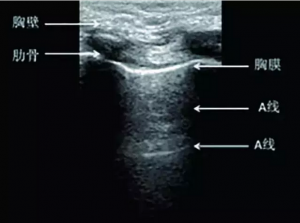

2.A线:与胸膜线平行的数条伪影线。